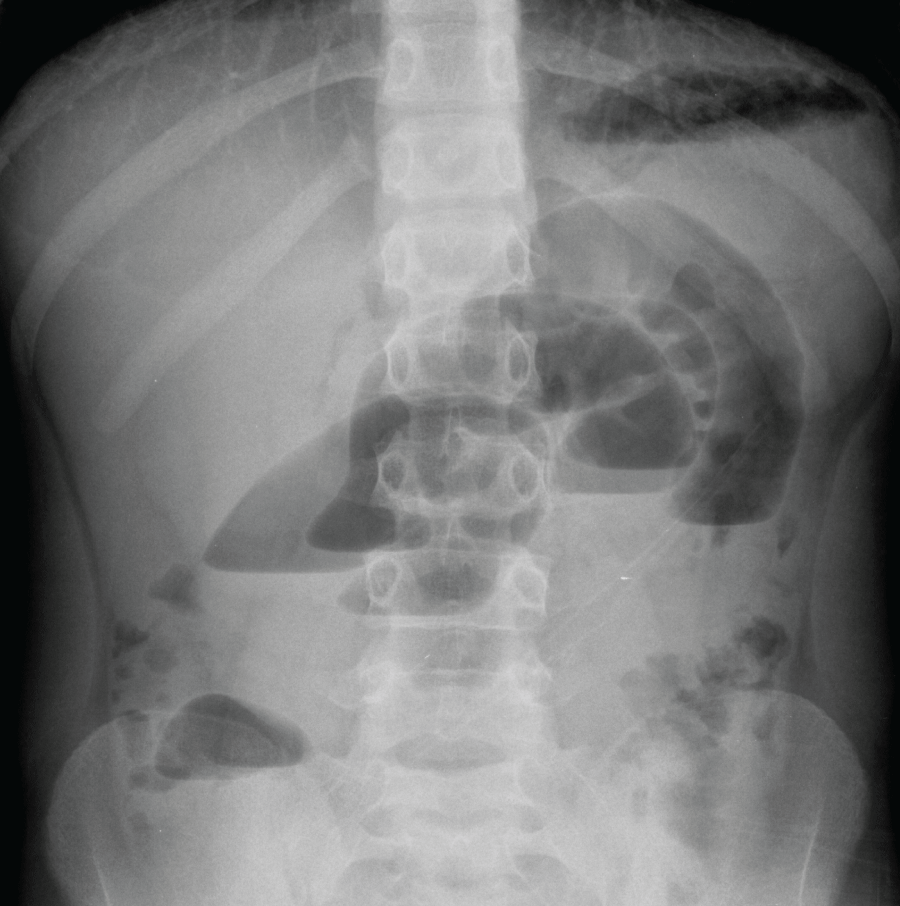

A 11-year-old boy with no relevant medical history was admitted to our emergency department because of colicky, diffuse abdominal associated to vomiting. He had regular bowel movements and no fever. At physical examination abdominal palpation was painful in the right lower quadrant and in mesogastrium with no rebound tenderness, peristalsis was reduced. Blood chemistries were normal. An abdominal plain X-ray study showed gas distension of some small bowel loops in the central region of the abdomen and some air-fluid levels. The abdominal ultrasound scan was normal except for some distended ileal loops filled with liquid in the lower part of the abdomen. The patient was admitted to our surgical ward for overnight clinical observation. Multiple attempts were made but it was not possible to place nasogastric tube for non-cooperation of the young boy. So whe performed repeated clinical evaluations and during the night the patient complained of intermittent pain. On the following morning he had biliary vomiting unresponsive to enema, blood chemistries were unchanged but a second plain abdominal X-ray study showed worsened conditions with the appearance of multiple air fluid levels suggesting a frank intestinal obstruction and warranting emergency surgery (Figure 1).